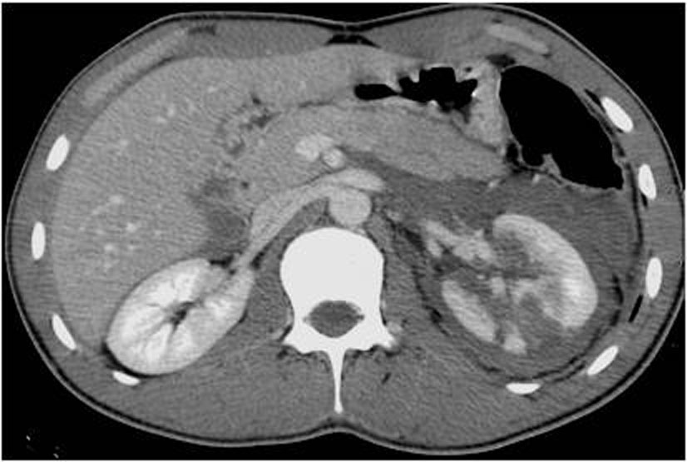

Renal injuries

Major:

• Deep medullary injuries with extravasation & Vascular injuries